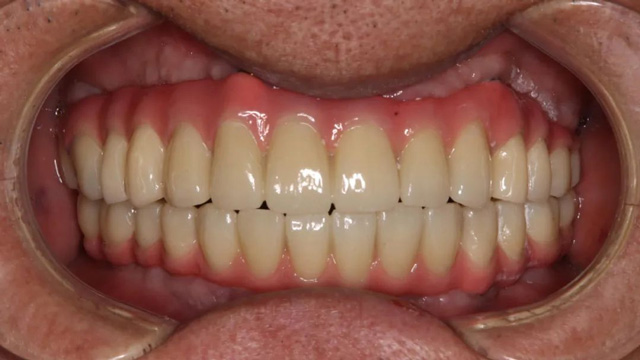

王先生正式戴牙后

王先生全口種植后戴冠

據(jù)李陽軍醫(yī)生介紹,對(duì)比檢查報(bào)告可以看到,王先生的骨量和牙周條件比2021年時(shí)差了很多,治療難度顯著增加。不僅如此,他因?yàn)橹暗闹委煼桨覆焕硐牒蛢深w種植體無法使用,最后承擔(dān)了更多的種植費(fèi)用,也承受了更長的缺牙期。